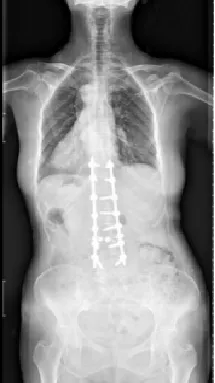

▷特发性脊柱侧凸

特发性脊柱侧凸是所有脊柱侧凸中最多见的,原因不明。其中青少年特发性脊柱侧凸(AIS)最常见,发病率1.5%-3%,占全部脊柱侧凸的75%-80%。约80%的AIS患者需佩戴支具以控制侧凸进展,佩戴支具的患者中,约1/4最终需要手术治疗。

▲ 女,14岁,青少年特发性脊柱侧凸